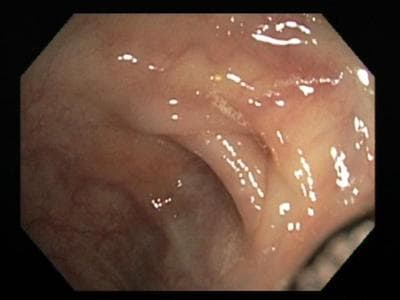

Dr. Horst immediately launched into some jokes, and soon I felt as if I’d gone to a bar with some friends. Of course, there were some major differences, such as the spectacular view on the screen of the pinkish tunnel with the skinny ridges encircling the passageway, looking the way one might imagine a hallway down the inside of a segmented worm. What is the evolutionary reason for the ridges, I wondered. Dr. Horst said he didn’t know of one, but he’d come up with a theory if I could write it up and make him famous.

The rest of the half hour long spelunking expedition was uneventful, with occasional unsettling, mildly uncomfortable moments, particularly at the sharp bends, and at one point, a mild burning sensation in my anus, which turned out to be insufficient lubrication, a problem which was quickly remedied. As for the inner terrain, the cleansing had been so successful that even in the upper reaches, almost nothing was visible except for the shimmering surface of my colon, which was devoid of even tiny polyps. (Healthy colons are thus, even on 90 year olds, because the epithelium gets replaced about every three weeks, said Dr. Horst.)